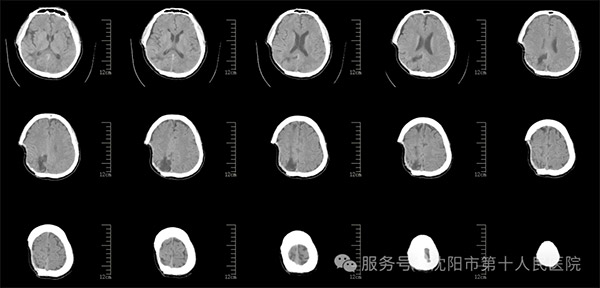

神经中心医生对患者进行外科专科治疗和康复促醒,景雪峰主任及其医护专业团队每日详细评估病情,及时制定用药方案,早期推进康复介入,耐心教授患者家属协同护理促进排痰和加强营养,在医护和家属共同努力下,患者逐渐苏醒康复。患者在经过一段时间治疗,各项功能大致恢复正常,但患者头部颅骨缺损,减压窗塌陷严重,容易发生脑摆动引起癫痫等不良情况,并且脑在没有颅骨保护的情况下,在日常生活中也不安全也影响美观。在患者进一步康复后,神经中心主任建议患者颅骨修补。

修补术前影像资料